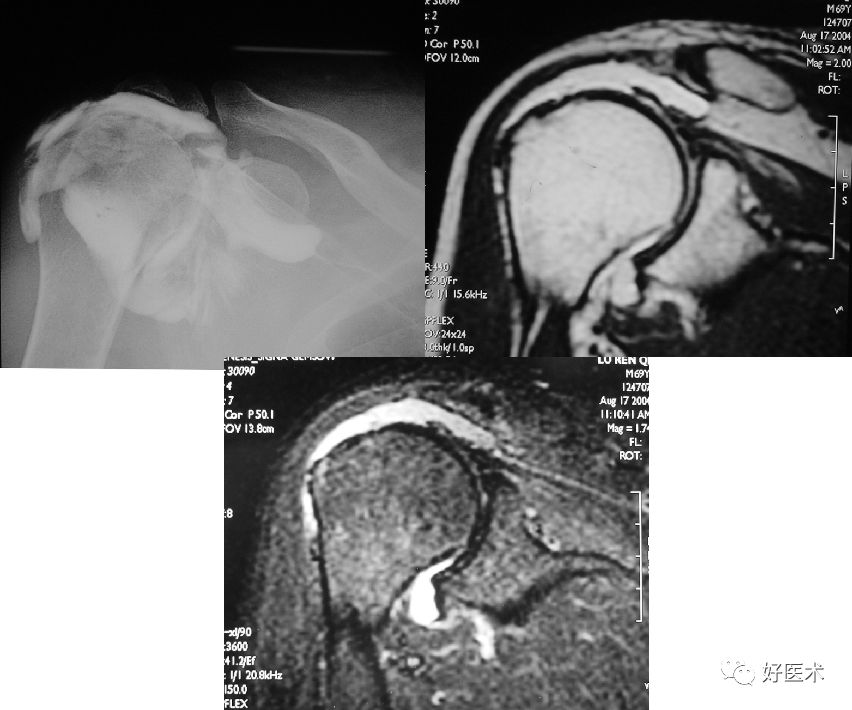

Bankart损伤的MR表现

-

三角形变钝

盂唇撕裂:关节盂唇软骨与盂缘可见线状高信号影并连续到关节面下

盂唇完全消失或盂唇明显移位

若盂唇损伤合并关节盂骨质损伤,称为骨性Bankart病变

骨性Bankart病变

MR间接关节造影1.5T轴位T1W脂肪抑制(TR=460s,TE=90s)

MR间接关节造影1.5T轴位T1W脂肪抑制

MR间接关节造影1.5T冠状面T1W脂肪抑制